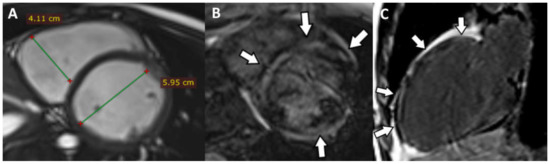

5. Cases Presentation